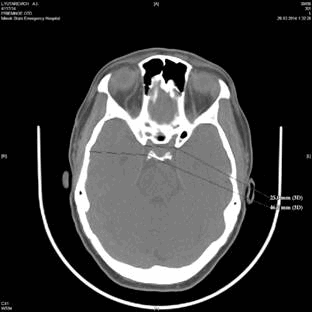

Двухмерные снимки в горизонтальной и сагиттальной плоскостях позволяют произвести необходимые измерения параметров черепа с точностью до 0,1 мм. Для удобства измерений рекомендуется отметить фиксированными координатами те или иные краниометрические точки на внутреннем основании и своде черепа, необходимые для измерения соответствующих параметров черепа. Для того, чтобы произвести измерение, необходимо воспользоваться инструментом «Электронная линейка». Измерение производится путем перетягивания курсора между краниометрическими точками. Результат отображается на мониторе справа в мм (рис. 2).

Рис. 2. Измерение краниометрических параметров в сагиттальной плоскости (слева) и в горизонтальной плоскости (справа)